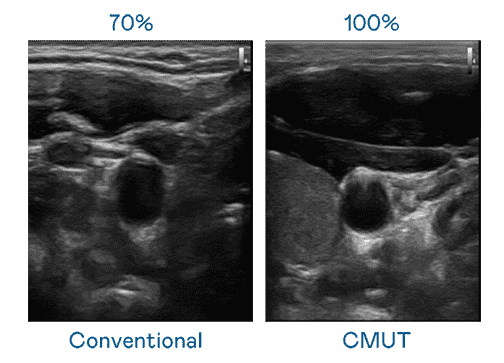

CMUT 技术是一种用电容式微机电元件来产生超音波讯号的技术。。。。与传统 PZT 压电式技术相比,,CMUT 频宽增加 30%,,,,更宽频的超音波讯号让影像解析度大幅提升,,是实现高影像品质医疗超音波扫描、、促进精准医疗发展的关键技术。。

大频宽带来超清晰影像

超音波影像的解析度高低,,首先取决于探头能发出的讯号频宽。。。。2121非凡 CMUT 可提供高清晰的超音波讯号,,提供高频宽、、高灵敏度、、、、影像纹理细节更高的超音波影像,,,协助医护人员缩短影像判读时间及利用精准的医疗影像进行诊断。。。。